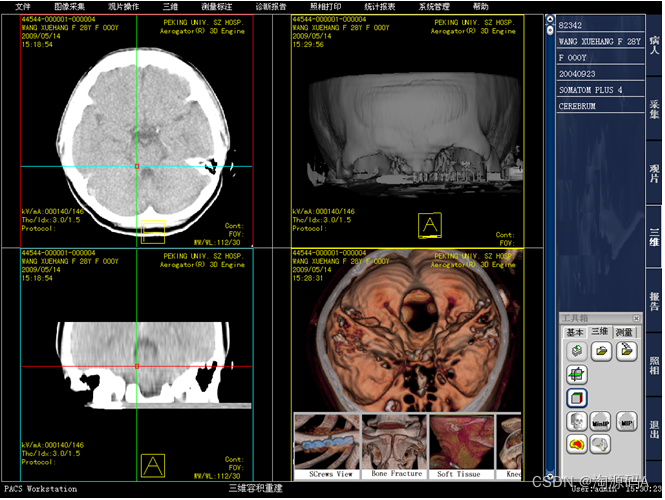

影像处理

图像显示:同屏分格显示病人不同体位、不同设备的图像,供诊断比较检查;显示矩阵任意调节;可自定义显示图像的相关信息,如姓名、年龄、设备型号等参数。

图像处理功能:提供窗宽/窗位调节,负像,图像漫游、缩放、旋转、镜像,动态视频捕捉,伪彩,播放等功能。

测量分析:长度、角度、面积测量,区域密度分析;显示感兴趣区R I分析,R I曲线。

图像标注:直线、箭头、矩形、椭圆、多边形、手画线、文本等格式标注等。

患者不同时期,不同成像设备的影像可对比诊断。

支持多屏和竖屏显示模式;支持专业厂商诊断级高分辨率、高亮度专业显示器。可利用快捷方式或快捷键执行相应功能。